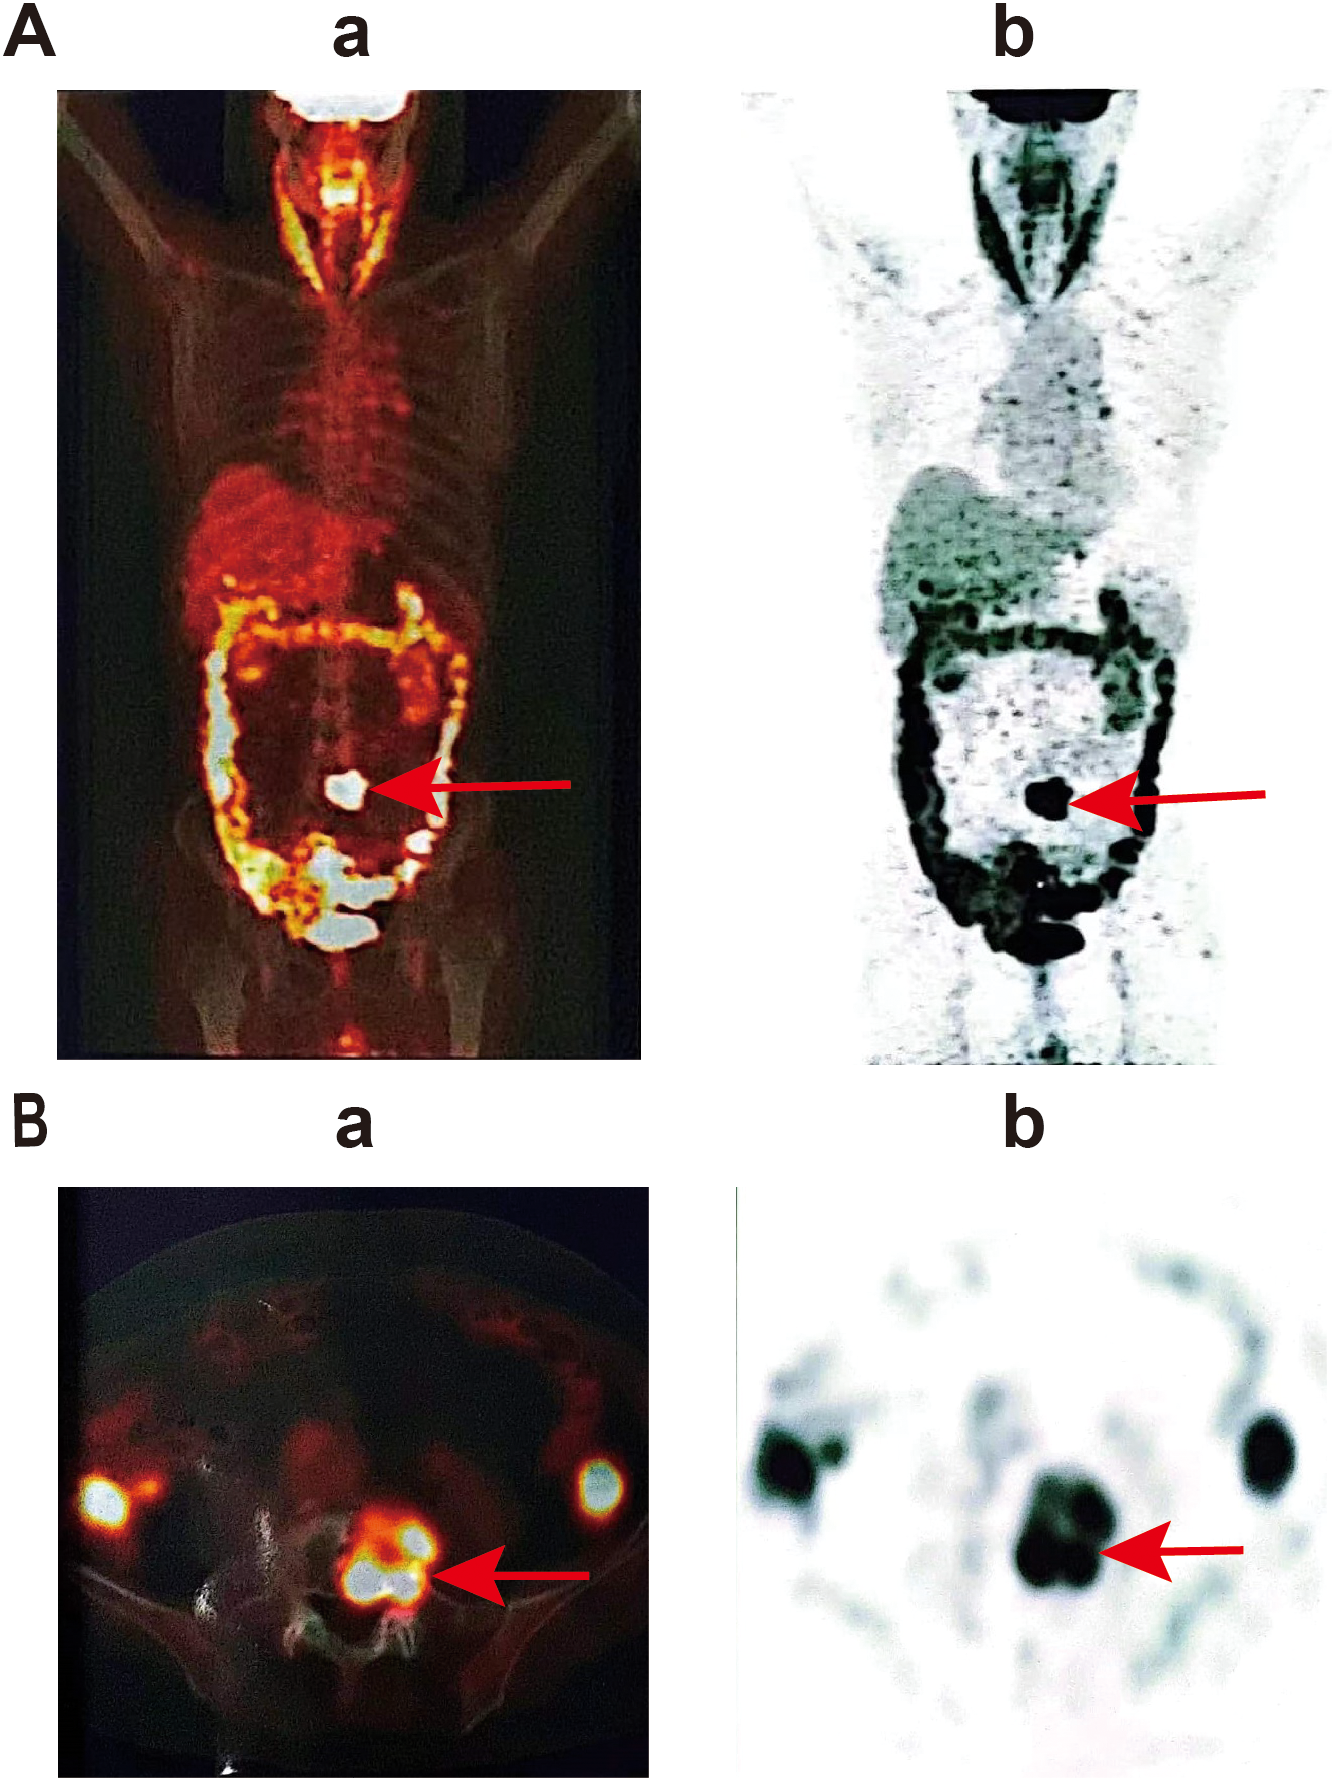

Lumbar MRI examination revealed abnormal signal intensity with T1 prolongation and T2 shortening in the left side of the L5 vertebral body and the left pedicle, accompanied by a protrusion toward the left posterior region. The anterior and superior margins of the vertebra exhibited irregular contours, and contrast-enhanced imaging demonstrated heterogeneous enhancement, suggestive of invasive changes, raising suspicion for tumor involvement (Figure 1A). Subsequent PET-CT examination identified osteolytic bone destruction with irregular borders, areas of sclerosis, and soft tissue mass formation in the corresponding region. Following intravenous administration of the tracer 18F-FDG, there was increased radiotracer uptake, with a maximum standard uptake value (SUV) value of 10.7, further supporting the likelihood of a neoplastic process (Figure 2). The blood test results showed no significant abnormalities.

Figure 2

PET-CT examination showed the lesion in L5. (a) Positron emission tomography image, (b) computed tomography image. (A) represents a whole-body scan image, showing the overall metabolic activity of the patient; (B) is a local scan image, which is a transverse view, and the area pointed to by the red arrow shows the high metabolic activity in the local region.